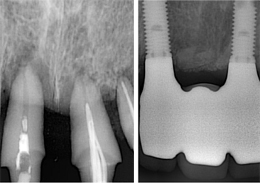

サイナスリフト

インプラント埋入前にサイナス部分にGBRを行い、骨が出来上がるのを待ってからインプラント治療を実施。

- 治療前の骨が足りていない状態

- サイナス部分にGBRを施し骨ができた状態

- 骨生成完了後インプラントを埋入し治療終了

- 主訴

- 上顎臼歯部の67欠損となり、上顎洞までの距離が不足したためインプラントの早期埋入が不可能であった

- 治療内容

- 上顎頬側よりラテラルウインドウ法で上顎洞底挙上術を行い2本のインプラントの埋入を行なった

- 治療費用

- 上顎洞底挙上術:150,000円(税別)、インプラント埋入1本:200,000円(税別)

- 治療期間

- 埋入手術までに6ヶ月